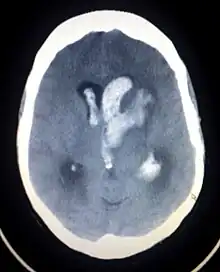

| CT scan of a spontaneous intracerebral bleed, leaking into the lateral ventricles | |

Intraparenchymal hemorrhage can be recognized on CT scans because blood appears brighter than other tissue and is separated from the inner table of the skull by brain tissue. The tissue surrounding a bleed is often less dense than the rest of the brain because of edema, and therefore shows up darker on the CT scan.[30] The oedema surrounding the haemorrhage would rapidly increase in size in the first 48 hours, and reached its maximum extent at day 14. The bigger the size of the haematoma, the larger its surrounding oedema.[31] Brain oedema formation is due to the breakdown of red blood cells, where haemoglobin and other contents of red blood cells are released. The release of these red blood cells contents causes toxic effect on the brain and causes brain oedema. Besides, the breaking down of blood-brain barrier also contributes to the odema formation.[13]